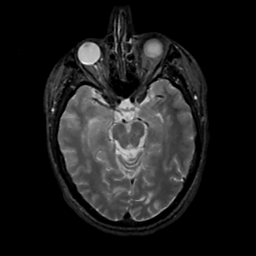

MR Study #1, February 10, 1991 -- Slice #19

[Home][Help][Clinical][Tour 1][Tour 2] Slice 19